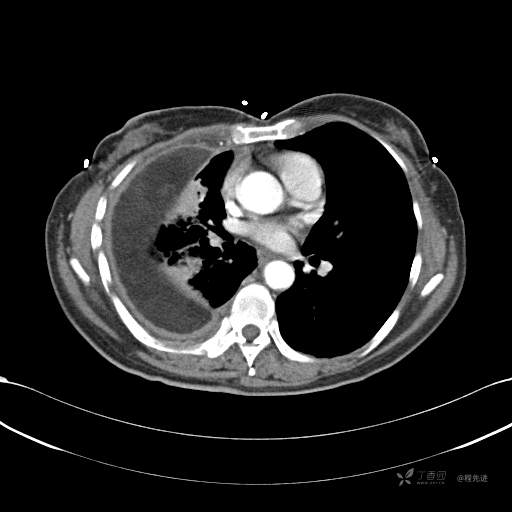

患者性别:女

患者年龄:51岁

简要病史:胸闷半年

肺淋巴管肌瘤病 (7)

乳糜胸 (8)